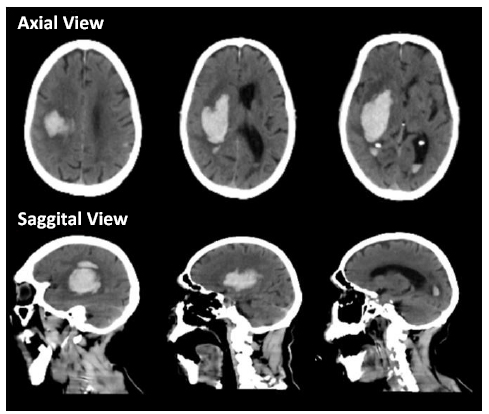

- Neuroradiology